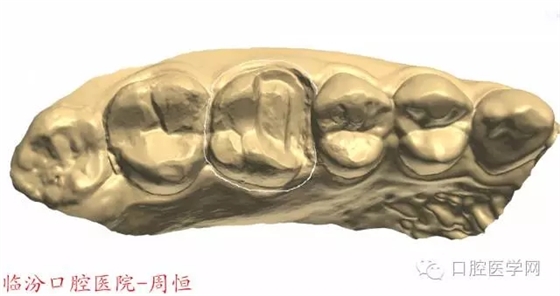

圖3 牙體預(yù)備前頜面觀